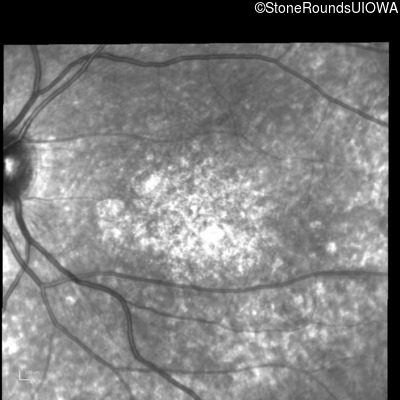

Infrared Fundus Photograph - Right - 10/160 sc

Exemplar

Infrared Fundus Photograph - Left - 10/200 sc